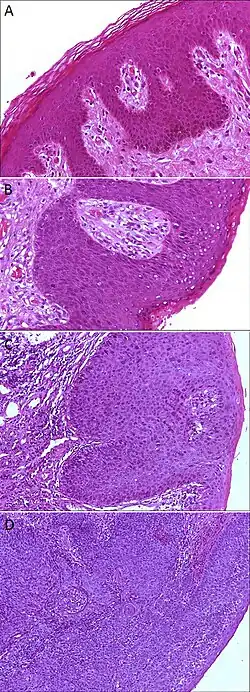

Epithelial dysplasia

A. Normal histology, negative for anal intraepithelial neoplasia lesion (AIN)

B. Low-grade dysplasia, here called low-grade squamous intraepithelial lesion (LSIL)

C. High-grade dysplasia, here called high grade squamous intraepithelial lesion (HSIL)

D. Squamous cell carcinoma, infiltrating the stroma (middle and left in image), and HSIL (right in image)